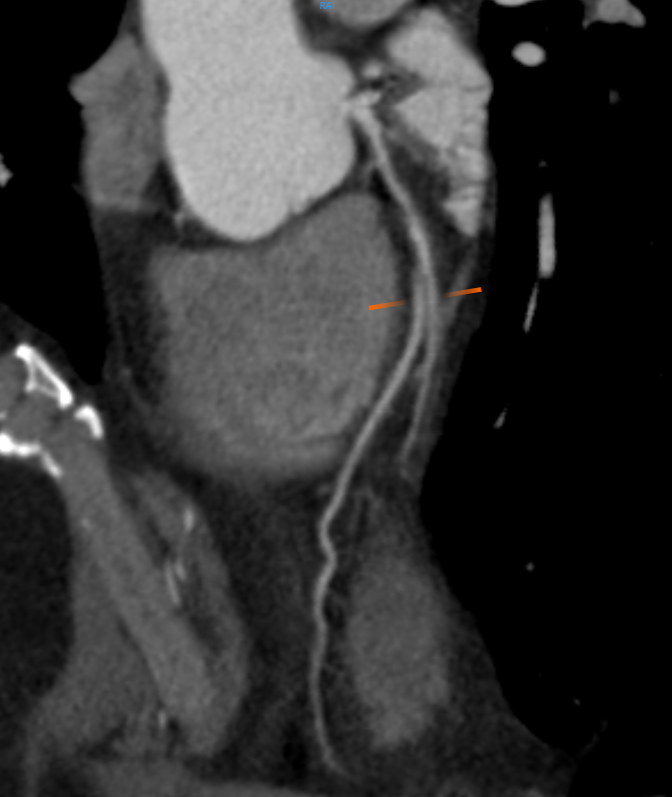

Coronary Artery Disease (CAD)

CT scan machines provide detailed images of the coronary arteries — the vessels that supply blood to the heart — enabling doctors to detect even early-stage plaque buildup, narrowing, or blockages that can restrict blood flow. By clearly revealing the location and severity of these obstructions, CT imaging helps guide treatment decisions, such as whether medication, angioplasty, or surgery is most appropriate. It also supports long-term monitoring of coronary artery disease progression, ultimately improving patient outcomes and reducing the risk of heart attacks.